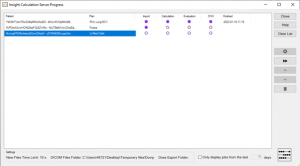

Prioritize calculations.

Prioritize calculations.- Support for acute patients.